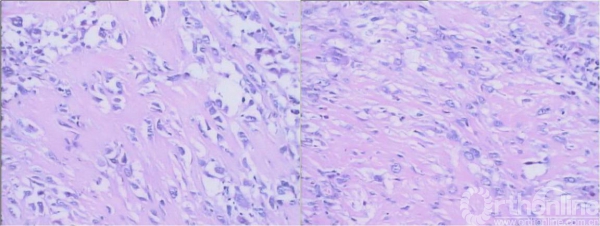

图15-10 第三次切开病理镜下表现

骨肉瘤。

图15-12 第三次术后大体病理镜下表现

图15-3第一次术后大体病理镜下表现

良性纤维性肿瘤。